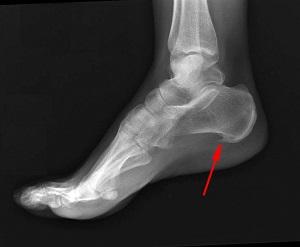

Название выбрано не случайно – на рентгене отображается костное уплотнение на пятке в виде шпоры.

На снимках рентгена отчетливо видны изменения строения голеностопа в результате образования шпоры, а УЗИ обнаруживает воспалительный процесс в мягких тканях. При пальпации пациент чувствует сильную боль, сравнимую с ходьбой босиком по осколкам.